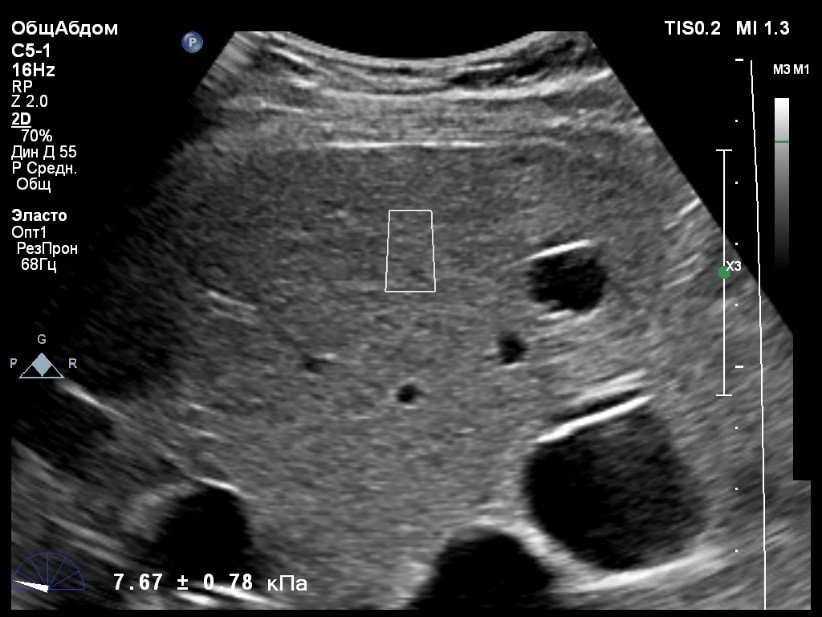

Пациент обратился к доктору с направлением на исследование степени жесткости печени в июне 2017 года. Из истории болезни, пациент страдает Гепатитом С с 2014 года. Лечение не получал. Транзиентная эластография показала не коррективные значения степени жесткости печени по причине сопутствующего поликистоза печени. На момент настоящего исследования, пациент не принимал пищу на протяжении 4 часов, АСТ, АЛТ не превышают патологических значений. Для оценки жесткости была выбрана технология компании Philips ElastPQ (точечная эластография) и прибор компании Philips Epiq 7 Исследование было проведено в соответствии с клиническими рекомендациями для ультразвуковых приборов компании Philips. В результате исследования были получены следующие результаты:

| 1 [7.95] kPa | 2 [8.73] kPa | 3 [8.11] kPa |

| 4 [9.32] kPa | 5 [8.05] kPa | 6 [9.52] kPa |

| 7 [8.66] kPa | 8 [7.36] kPa | 9 [8.54] kPa |

| 10 [8.30] kPa | 11 [6.56] kPa | 12 [7.14] kPa |

| 13 [7.47] kPa | 14 [6.56] kPa | 15 [6.56] kPa |

Стандартное Отклонение [0.85] kPa Медиана Жесткости [8.05] kPa Фактор Качества IQR/Med 10%

Зона интереса расположена на более чем на один сантиметр глубже капсулы, параллельно ходу луча, в середине изображения, в участке печени лишенном кист.

Капсула видна как белая линия перпендикулярная ходу ультразвукового луча, исследования производятся приблизительно в одном и том же сегменте печени.

Стандартное отклонение (2,26 kPA) не превышает 30 процентов от полученного значения (8,54 kPA).

Для интерпретации полученных клинических данных были использованы Рекомендации по проведению эластографии сдвиговой волной для оценки жесткости печени при использовании ультразвуковых аппаратов компании Филипс с примером протокола. Техническая сложность проведения слепой эластометрии печени связана с сопутствующим поликистозом органа и диагностическим методом выбора в данной ситуации является Эластография с возможностью визуального контроля положения контрольного объема. Подготовка пациента соответствовала проводимому исследованию. Представленные слайды проведенного исследования свидетельствуют о правильном техническом исполнении проб, отсутствием в поле контрольного объема кистозных образований, что позволяет заключиться о достоверности полученных измерений. Таким образом, учитывая полученную медиану жесткости на уровне 8,05 кРа (6.56 – 9.52 kPa) и уровень стандартных отклонений не превышающих 30%, полагаю, что уровень степени фиброза соответствует стадии F2. Заведующий отделением УЗД МЦ «Асклепий», Глушенко Д. Е.